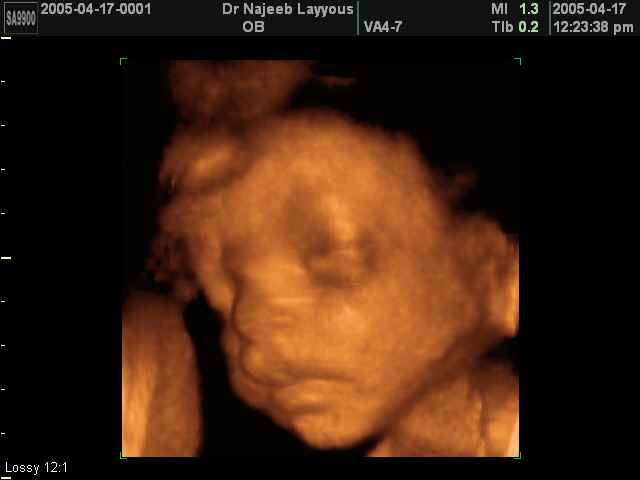

صور لتصرفات الجنين داخل الرحم بجهاز الالتراساوند ثلاثي الأبعاد | الدكتور نجيب ليوس

صور بجهاز الموجات فوق صوتية ثلاثي الأبعاد لتصرفات الجنين داخل الرحم